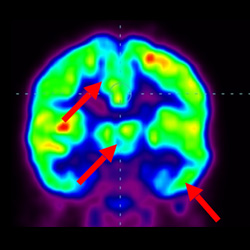

細胞治療后,藍色和黑色區域減少,并且看到更活躍的區域。這表明損傷減少并改善了大腦功能。

這證明細胞療法是治療腦癱兒童安全有效的方法。細胞療法可以更新大腦損傷的核心,并且可以通過 PET CT 掃描來監測大腦的改善情況。這些細胞療法與標準治療一起促進腦癱兒童的生長和改善。